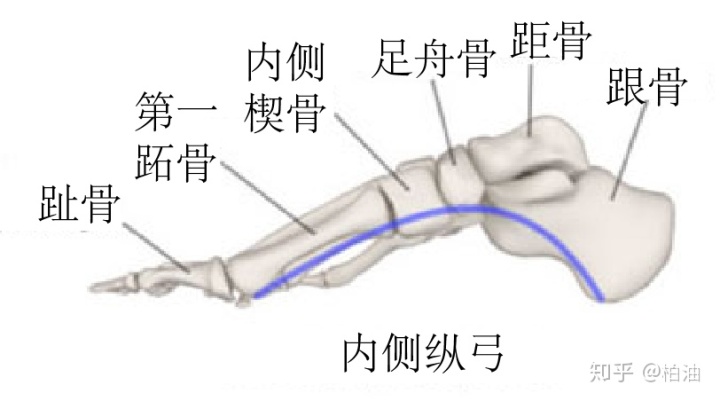

左侧脚底的ABC三点是我们正常站立时足部的三个支撑点,这三个点每两个点之间就形成了一个足弓。所以,人的每只脚都有三个足弓,分别是内侧纵弓(A-C)、外侧纵弓(B-C)、横弓(A-B),我们平常说的足弓一般指的就是内侧纵弓。

内侧纵弓也是三个足弓中最重要的,它是怎么形成的呢?

图上显示了内侧足弓相关的骨骼,包括第一跖骨、内侧楔骨、足舟骨、距骨和根骨。

这些骨骼和骨骼之间的韧带构成了足弓的刚性基础,但光有这些还不够,还需要有肌肉参与支撑,而且这种支撑是动态的。

主要的支撑肌肉包括:踇收肌、胫骨后肌、腓骨长肌、踇长屈肌。通过这些肌肉的收缩和拉长,维持足弓在运动过程中的动态稳定。

此外,内侧足弓的形成还需要足底软组织的参与,包括足底长韧带、弹性韧带、足底筋膜等。

这些组织是否处于正常的位置、是否维持正常的功能对于足弓的稳定至关重要,我们常说的扁平足指的就是维持足弓的内侧楔骨下移造成的,同时距骨和足舟骨向内侧移动,严重的情况下距骨的高度也会下降。这也是为什么有扁平足的同学,在双脚并拢站立时,两只脚的脚踝内侧会碰到一起。